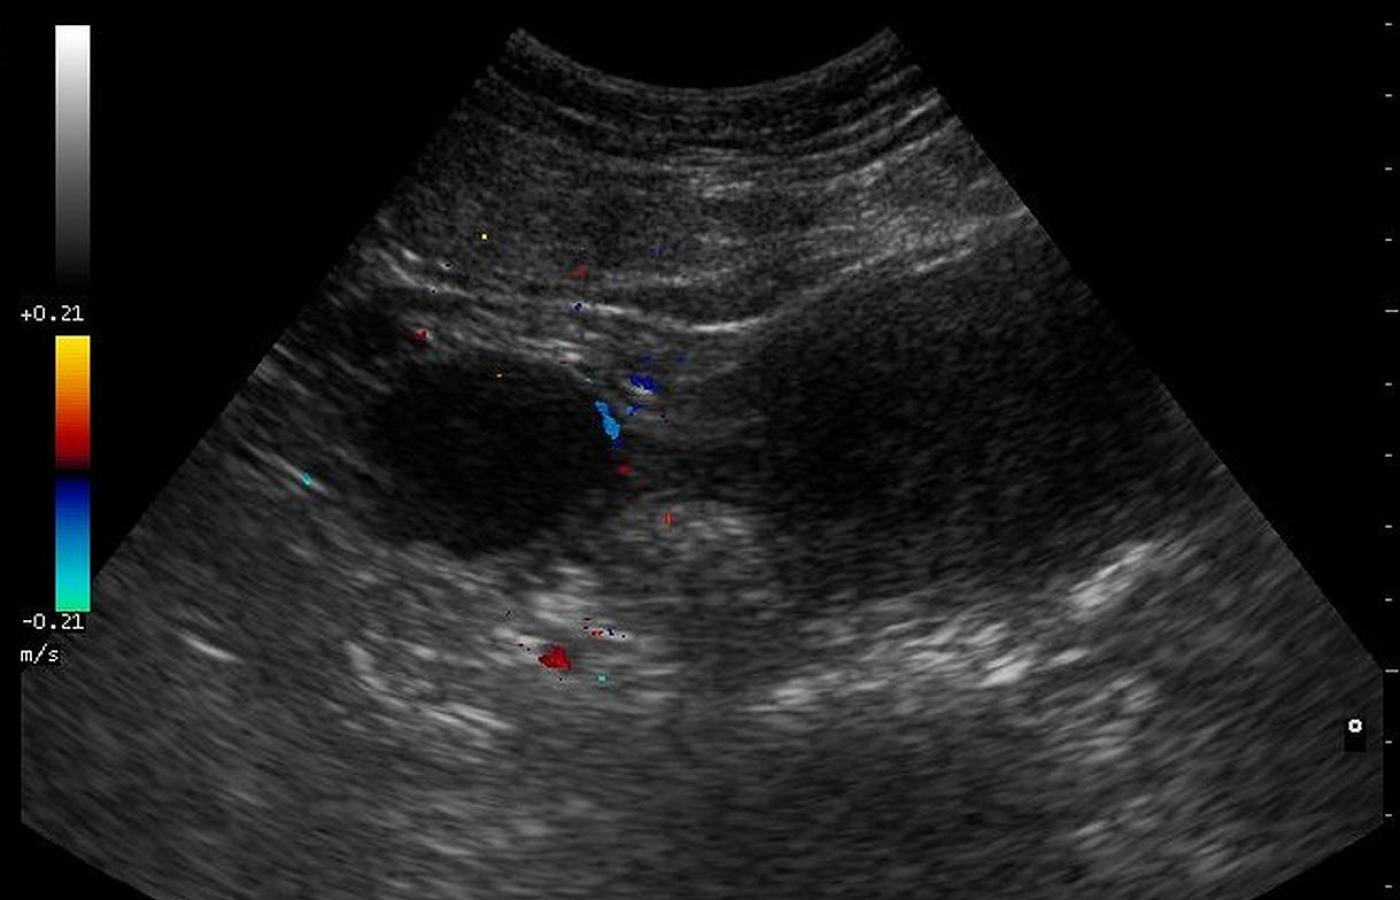

Ultrasonograficzny obraz jajników.Nevit Dilmen/Wikipedia Ultrasonograficzny obraz jajników.